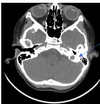

Co to za schorzenie? (wrodzone)

Perlak wrodzony